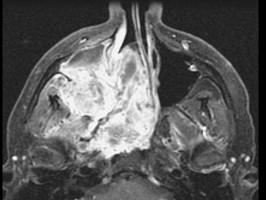

问题 15岁,男性,渐进性鼻塞1年余,MRI扫描如图所示,请选择最可能诊断 ( )

选项 A、鼻咽部囊肿 B、鼻咽癌 C、鼻咽部脓肿 D、脊索瘤 E、鼻咽部纤维血管瘤

答案 E